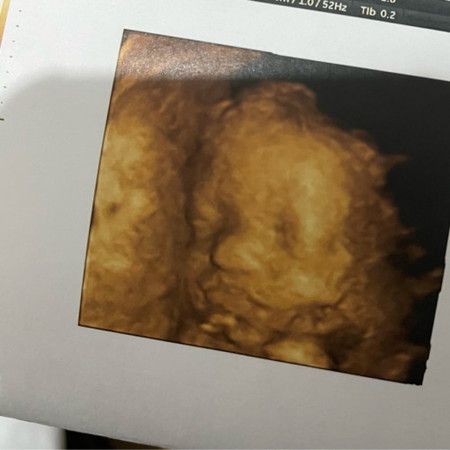

ดูเหมือนปากแหว่งมั้ยคะ ตอนไปซาวด์หมอบอกว่าไม่มีอะไรผิดปกติค่ะ ตอนอยู่คลีนิคยังเห็นรูปไม่ชัดเลยไม่ได้ถามหมอ กลับบ้านพึ่งมาดูรูปดีๆ กังวลนิดหน่อยค่ะ

ไม่ค่ะแม่ ถ้าน้องผิดปกติคุณหมอจะแจ้งแม่ทันทีนะคะ ของบ้านนี้ตอนซาวก็มีอะไรมาบัง ปากก็เป็นขีดๆเหมือนกัน แต่ดูหลายๆมุมก็ปกติดีค่ะแม่